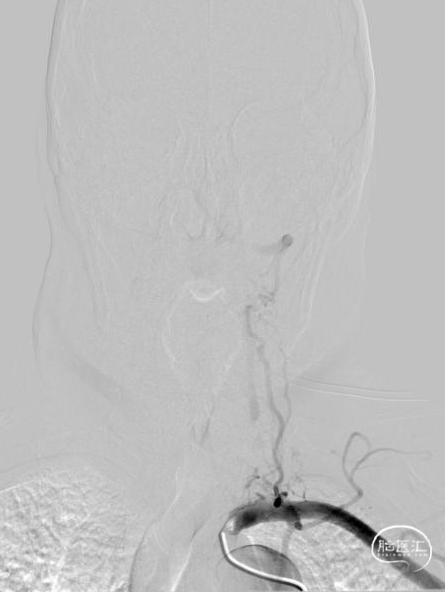

➢术后即刻影像

➢术后定期随访情况

术中造影证实右椎纤细、右椎V4段可见微弱血流入基底动脉、左椎动脉开口闭塞、颈升动脉通过侧支循环向左椎V3供血并逆流至V1中段、左椎V4轻度狭窄;

对于该类病变我们的最优选择就是处理左侧椎动脉起始部。针对路径迂曲,其实当我们的微导丝通过病变到达左椎V3段时可明显看见血管拉直,迂曲的管径问题迎刃而解;